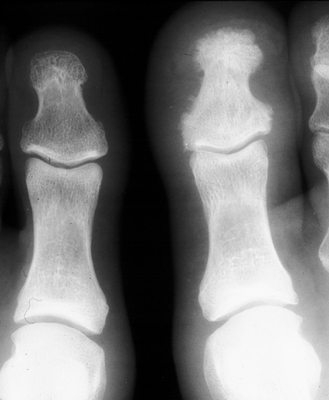

Single x-ray of the toes revealing increased density throughout the osseous structures of the involved digit in a person with psoriatic arthritis. Sclerosis of an entire phalanx, typically the great toe, is likely the result of bony proliferation as an exaggerated healing response to injured bone in patients with seronegative spondyloarthropathy.

bulletResnick D, Broderick TW: Bony proliferation of terminal toe phalanges in psoriasis: the "ivory" phalanx. J Can Assoc Radiol 1977 Sep;28(3):187-9.          [See related articles]